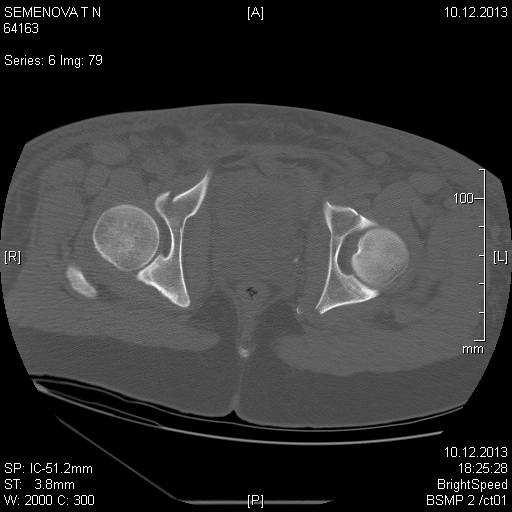

Доброго времени суток коллеги! Прошу вас, подсказать тактику в решении

оперативного лечения следующего сложного повреждения таза. Был ли опыт в

фиксации подобных повреждений?

Травма 03.12.2013,больная переведена из лечебного учреждения соседней

области. На данный момент у больной следующий диагноз: ЗЧМТ,сотрясение

головного мозга;Закр. травма грудной клетки,множественные переломы ребер

справа с повреждением ткани легкого, правосторонний гемопневмоторакс,

состояние после торакоцентеза; Закр.травма живота,разрыв

селезенки,гемоперионеум, состояние после лапаротомиии спленэктомии;

Закр. оскольчатый перелом сред-верх\3 левой бедренной кости, состояние

после накостного металлостеосинтеза; Закр.поперечный переломовывих на

уровне S1S2, многооскольчатый перелом латеральных масс крестца с обеих

сторон,перелом обеих лонных и седалищных костей.

Перелом поперечных отростков L1,L2,L3,L4, L5 позвонка справа. ШОК 3ст.

Вкратце изложил диагноз.

В настоящее время состояние больной тяжелое. Первым этапом планируем

наложить АНФ (переднюю раму) После стабилизации состояния необходимо

будет выполнить фиксацию.

Имеется один вопрос - какие импланты необходимы т.е. в какой комбинации

и какая последовательность фиксации?